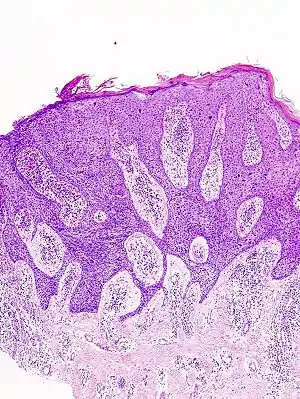

![]() Гістологічна картина хвороби Боуена Гістологічна картина хвороби Боуена | |